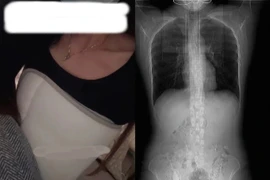

Tờ SCMP đưa tin một phụ nữ Thượng Hải tên Huang đột ngột lên cơn ho sau khi ăn thức ăn cay. Cô không ngờ rằng cơn ho đó khiến bản thân gãy 4 xương sườn, phải quấn băng quanh ngực trong 1 tháng.